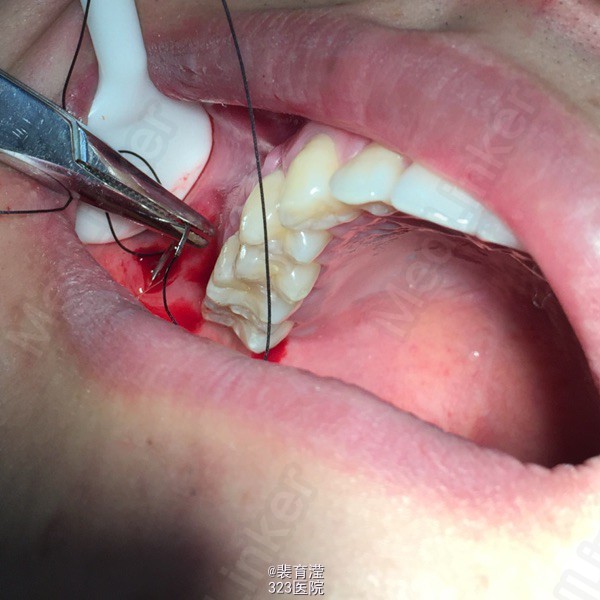

诊断:异物囊肿 右下第三磨牙阻生 处理:1.局麻下切除异物囊肿,缝合,止血。 2.右下第三磨牙局麻下 拔除 搔刮牙槽窝 止血。

随访:口服消炎药 ,止疼药后无不适,一周后拆线 讨论:阻生齿拔除 先去处阻力。